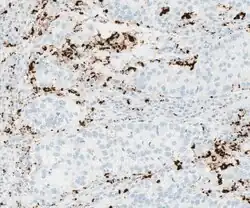

PD-L1-Diagnostik

Für die Therapie PD-L1-positiver Tumoren werden verschiedene Scoring-Typen eingesetzt:

- Tumor Proportion Score (TPS, prozentualer Anteil PD-L1-positiver Tumorzellen von allen vitalen Tumorzellen)

- Immune Cell Score (IC, prozentualer Anteil der Fläche PD-L1-positiver Immunzellen von der Fläche der vitalen Tumorzellen)

- Combined Positive Score (CPS, Kombination von TIPS und IC), prozentualer Anteil PD-L1-positiver Zellen einschließlich Lymphozyten und Makrophagen von allen vitalen Tumorzellen

- Tumor Area Positivity Score (TAP-Score, prozentualer Anteil der Fläche an PD-L1-positiven Tumor- und Immunzellen an der Gesamttumorfläche)